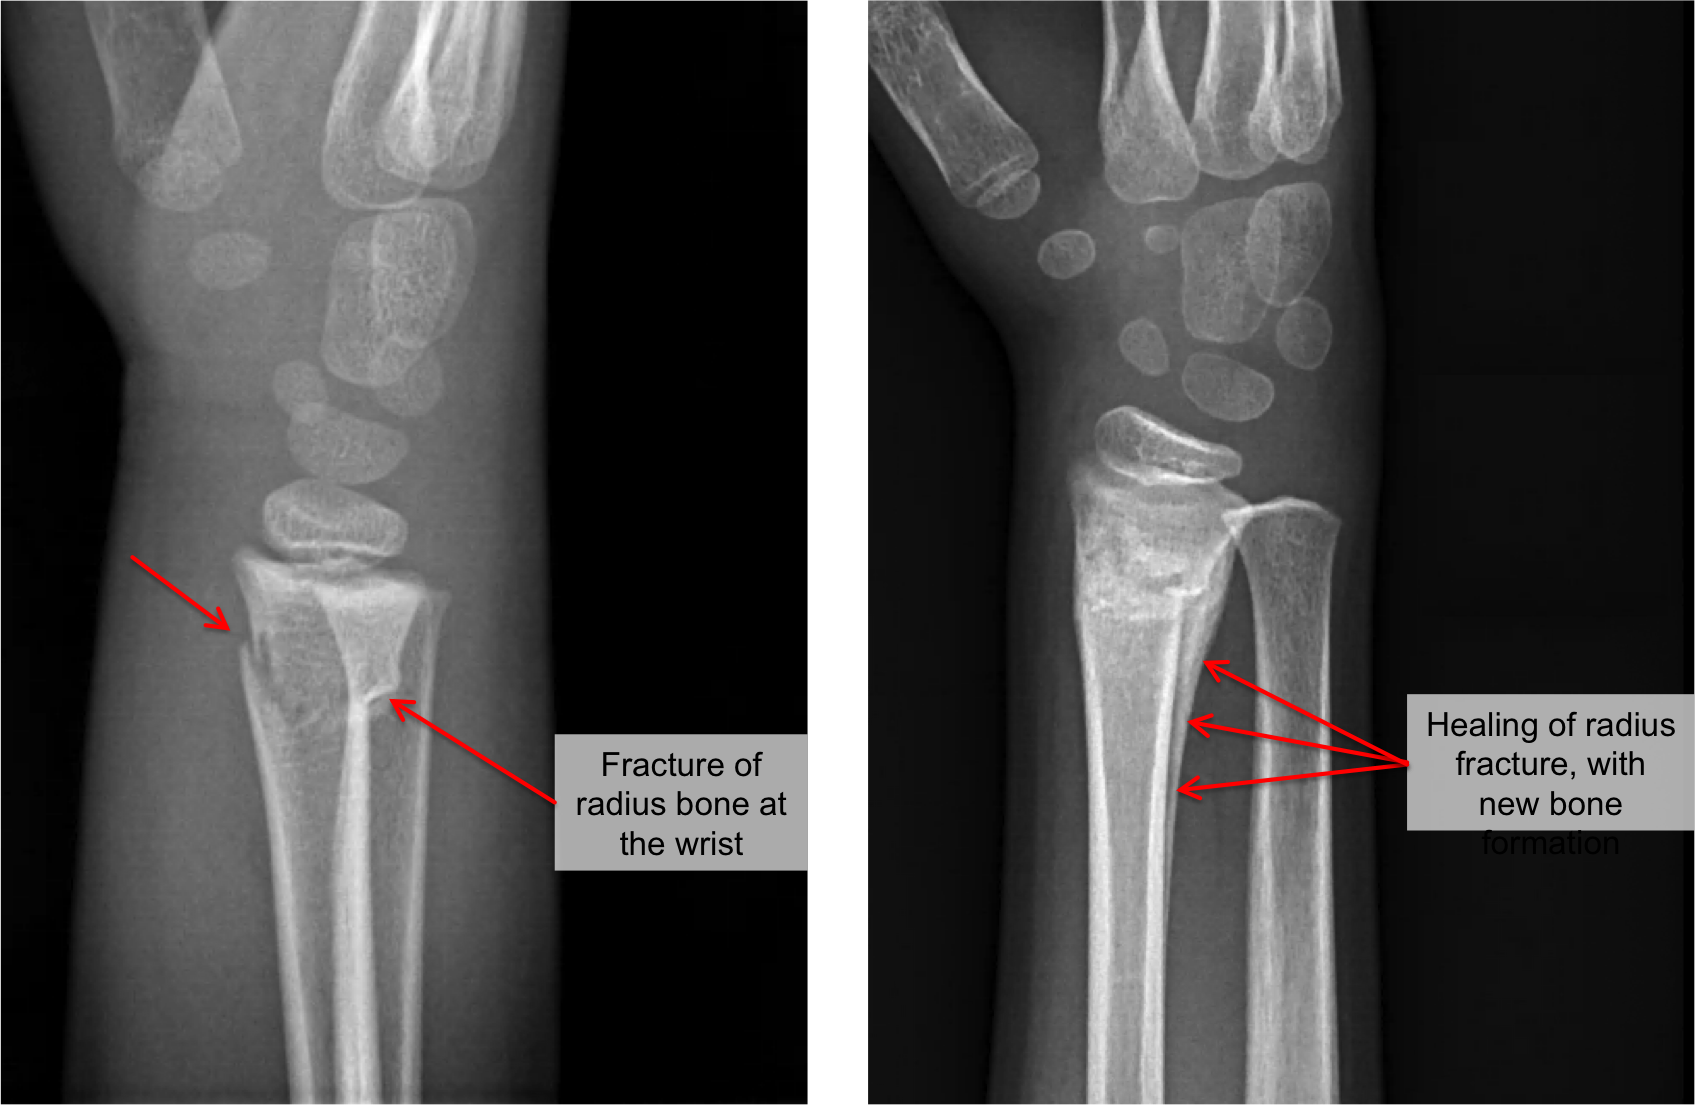

Buckle Fracture Symptoms Causes Treatment 2025, Buckle fracture of the wrist CUH 2025, Buckle Fracture Raleigh Hand Surgery Joseph J. Schreiber MD 2025, Fracture How to treat a buckle fracture of the distal radius 2025, Torus fracture Wikipedia 2025, Buckle fracture 2025, Kidshealth Buckle Fractures Akron Children s 2025, Buckle fractures of the distal radius in children CMAJ 2025, How to Care for Your Child with Buckle Fracture Sidra Medicine 2025, Kids Health Information Fracture care buckle injury 2025, The Pediatric Wrist Buckle Fracture is Common Louisville Bones 2025, Buckle fracture 2025, Forearm Fractures Children s Mercy Kansas City 2025, Buckle Fracture Raleigh Hand Surgery Joseph J. Schreiber MD 2025, Buckle Fractures Rady Children s Hospital 2025, Greenstick Buckle Fracture Activate Physiotherapy 2025, What are Buckle Fractures WristSupports 2025, Buckle Greenstick Fracture of the Distal Radius Sports 2025, Choosing Wisely Distal Radius Buckle Fractures CanadiEM 2025, Buckle Greenstick Fracture of the Distal Radius Sports 2025, Clinical Practice Guidelines Distal radius and or ulna 2025, Buckle fracture Radiology at St. Vincent s University Hospital 2025, Radiology Case 5 SpringerLink 2025, Buckle fracture of the wrist Resource Library Sheffield 2025, Forearm Fractures Children s Mercy Kansas City 2025, Buckle fracture Radiology Case Radiopaedia 2025, Fracture How to treat a buckle fracture of the distal radius 2025, Buckle fracture in a girl age 2 years 3 months who presented to 2025, Greenstick Fracture or Paediatric Fracture Treatment 2025, Buckle fracture Radiology Case Radiopaedia 2025, Buckle Fracture by Dr. David Nelson MD 2025, Pondering Paeds Buckle In 2025, State of the Art Pediatrics Buckle Fractures in Children 2025, OrthoKids Forearm Fractures 2025, Buckle Greenstick Fracture of the Distal Radius Sports 2025.

Buckle Fracture Symptoms Causes Treatment 2025, Buckle fracture of the wrist CUH 2025, Buckle Fracture Raleigh Hand Surgery Joseph J. Schreiber MD 2025, Fracture How to treat a buckle fracture of the distal radius 2025, Torus fracture Wikipedia 2025, Buckle fracture 2025, Kidshealth Buckle Fractures Akron Children s 2025, Buckle fractures of the distal radius in children CMAJ 2025, How to Care for Your Child with Buckle Fracture Sidra Medicine 2025, Kids Health Information Fracture care buckle injury 2025, The Pediatric Wrist Buckle Fracture is Common Louisville Bones 2025, Buckle fracture 2025, Forearm Fractures Children s Mercy Kansas City 2025, Buckle Fracture Raleigh Hand Surgery Joseph J. Schreiber MD 2025, Buckle Fractures Rady Children s Hospital 2025, Greenstick Buckle Fracture Activate Physiotherapy 2025, What are Buckle Fractures WristSupports 2025, Buckle Greenstick Fracture of the Distal Radius Sports 2025, Choosing Wisely Distal Radius Buckle Fractures CanadiEM 2025, Buckle Greenstick Fracture of the Distal Radius Sports 2025, Clinical Practice Guidelines Distal radius and or ulna 2025, Buckle fracture Radiology at St. Vincent s University Hospital 2025, Radiology Case 5 SpringerLink 2025, Buckle fracture of the wrist Resource Library Sheffield 2025, Forearm Fractures Children s Mercy Kansas City 2025, Buckle fracture Radiology Case Radiopaedia 2025, Fracture How to treat a buckle fracture of the distal radius 2025, Buckle fracture in a girl age 2 years 3 months who presented to 2025, Greenstick Fracture or Paediatric Fracture Treatment 2025, Buckle fracture Radiology Case Radiopaedia 2025, Buckle Fracture by Dr. David Nelson MD 2025, Pondering Paeds Buckle In 2025, State of the Art Pediatrics Buckle Fractures in Children 2025, OrthoKids Forearm Fractures 2025, Buckle Greenstick Fracture of the Distal Radius Sports 2025.